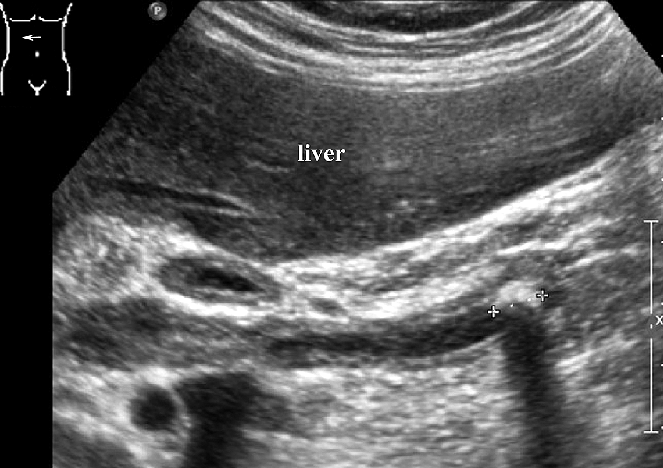

Imaging studies (ultrasound, CT scan, MRI)

Ultrasonography, computed tomography, and magnetic resonance cholangiopancreatography are three noninvasive imaging techniques for people with jaundice. Ultrasonography or computed tomography is typically the first-line option for evaluating blockage, cirrhosis, and vascular patency, with ultrasonography being the least intrusive and most cost-effective method. Magnetic resonance cholangiopancreatography or endoscopic retrograde cholangio- pancreatography can be used to see the intra- and extrahepatic biliary tree further, with the latter allowing for treatment options such as biliary stent implantation to ease blockage. Endoscopic ultrasonography, in conjunction with endoscopic retrograde cholangiopancreato- graphy, can evaluate common bile duct blockages and distinguish between a mass and a stone.

Fig 2. Ultrasound